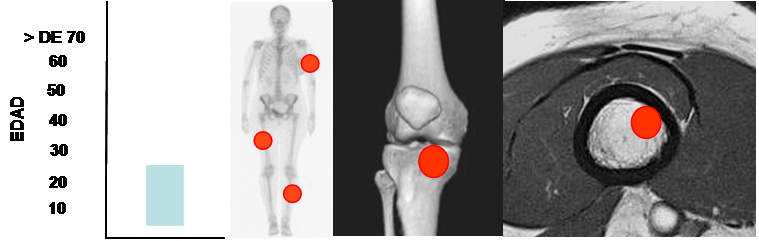

Fig 81. Condroblastoma.

Mayor frecuencia entre los 5 y 25 años. Predominio en los huesos largos.

Lesión epifisiaria, de ubicación excéntrica.